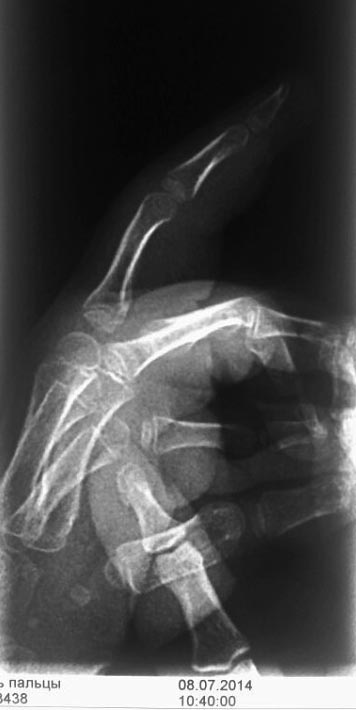

первый снимок через месяц после травмы.

второй снимок через 2 месяца после травмы. И снимок через 5 месяцев прямая проекция. Боковая проекция через 5 мес указана в самом начале